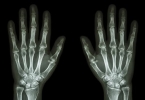

• 风湿性关节炎早期夹板固定

风湿性关节炎早期夹板固定

风湿性关节炎早期可通过夹板固定缓解症状。主要作用包括减轻关节负担、防止畸形发展、降低炎症反应、促进局部休息、延缓病情进展。1、减轻关节负担:夹板固定通过限制关节活动范围,减少关节面摩擦和压力。尤其适用 ...